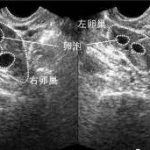

第三代试管婴儿流程